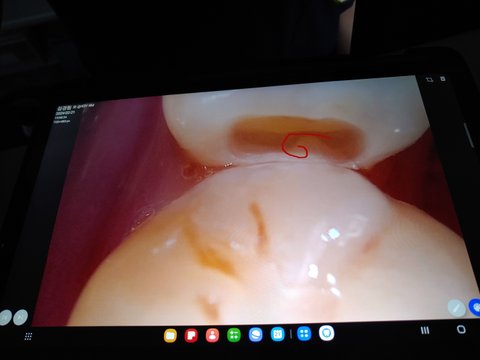

의사쌤은 입안을 보시더니

오른쪽에는 상처가 나있는 것을 보시고

그런데 잇몸 사진을 보시더니

왼쪽 위에 마모되있어서 씌워야하고

왼쪽 아래 어금니는 충치치료받아야한다고